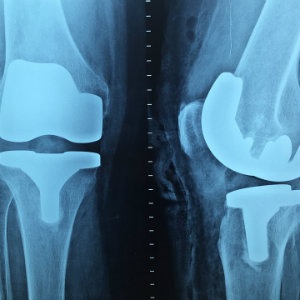

xray of kneescast on two broken fingers